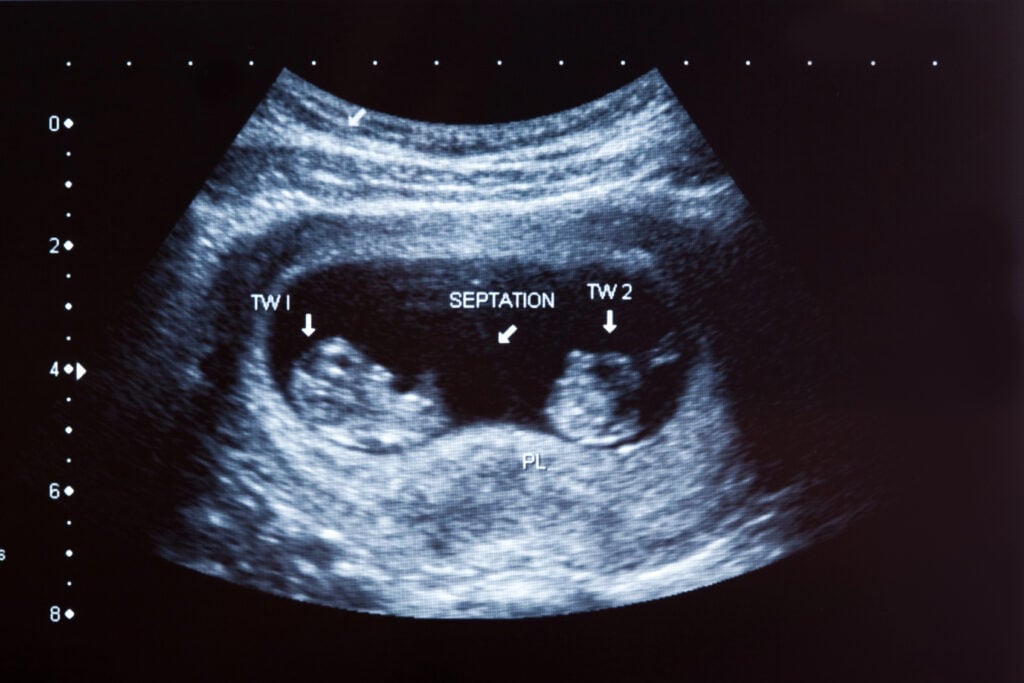

- Carrying twins, triplets, or more